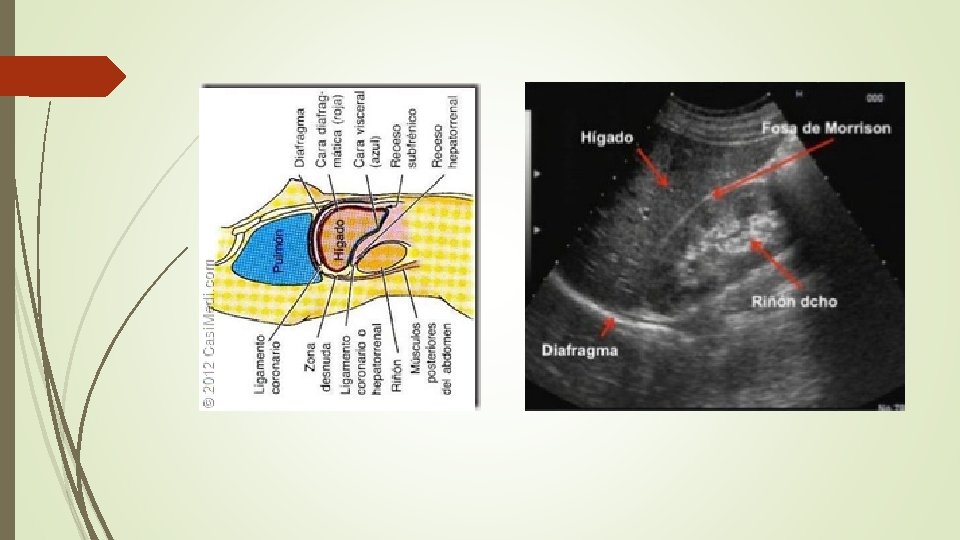

1. - RECESO HEPATORRENAL (Fosa de Morrison) Plano SAGITAL, línea media axilar derecha 10ª-11ª costilla. CRANEAL CAUDAL

Evaluar 1. Liquido en fosa de Morrison Coagulo = Ecogénico

TRANSVERSA L SAGITA L CRANEAL CAUDAL DERECHA IZQUIERD A

2. Liquido en polo renal inferior 3. Liquido debajo del diafragma

4. Liquido/aire supradiafragmático (hemo o neumotórax) E-FAST (FAST EXTENDIDO)